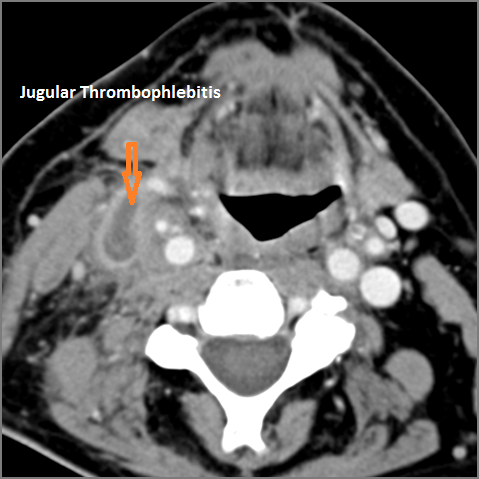

Vascular Findings

There is evidence of thrombus, thrombophlebitis or other occlusive or inflammatory process of the jugular vein or smaller venous tributaries. [Yes/No]

There is evidence of thrombus, inflammation of the common, external or internal carotid artery. [Yes/No]